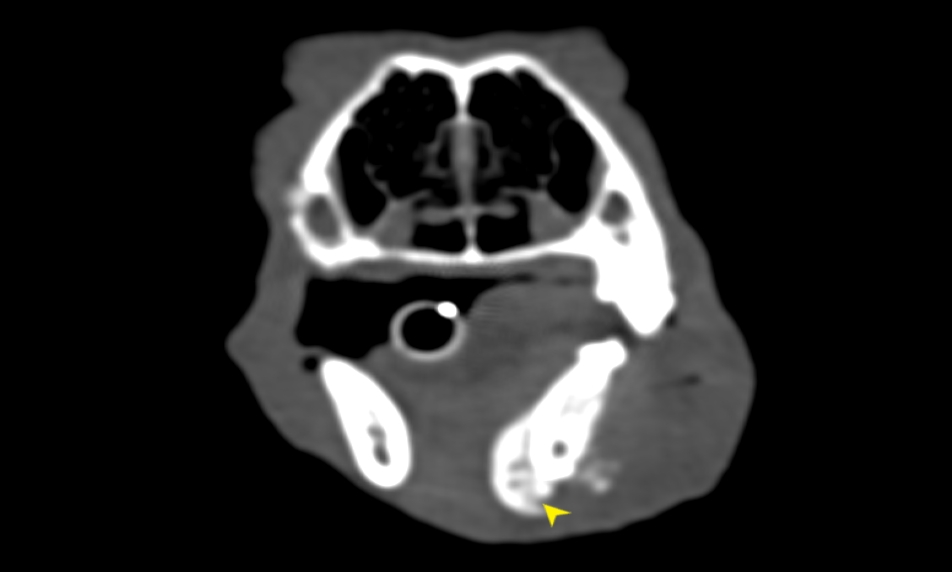

狗狗電腦斷層掃描 不明原因口腔出血 嚴重牙周病 口腔惡性腫瘤 鱗狀上皮細胞癌(Squamous cell carcinoma,SCC)

主訴嘴巴突然流血 口腔潰爛 左下顎腫脹 同時有嚴重牙周病 經由口腔採樣 電腦斷層掃描 確認為鱗狀上皮細胞癌(Squamous cell carcinoma,SCC)同時已經侵犯下顎骨。確診後經由外科醫師、腫瘤科醫師、電腦斷層影像科醫師共同擬定治療計畫後

,大範圍切除左下顎,經過一年追蹤,目前狗狗一切安好喔。

*電腦斷層影像